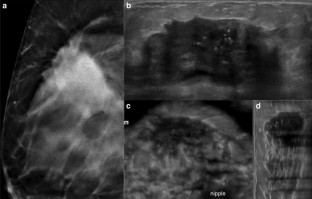

Fig. 2